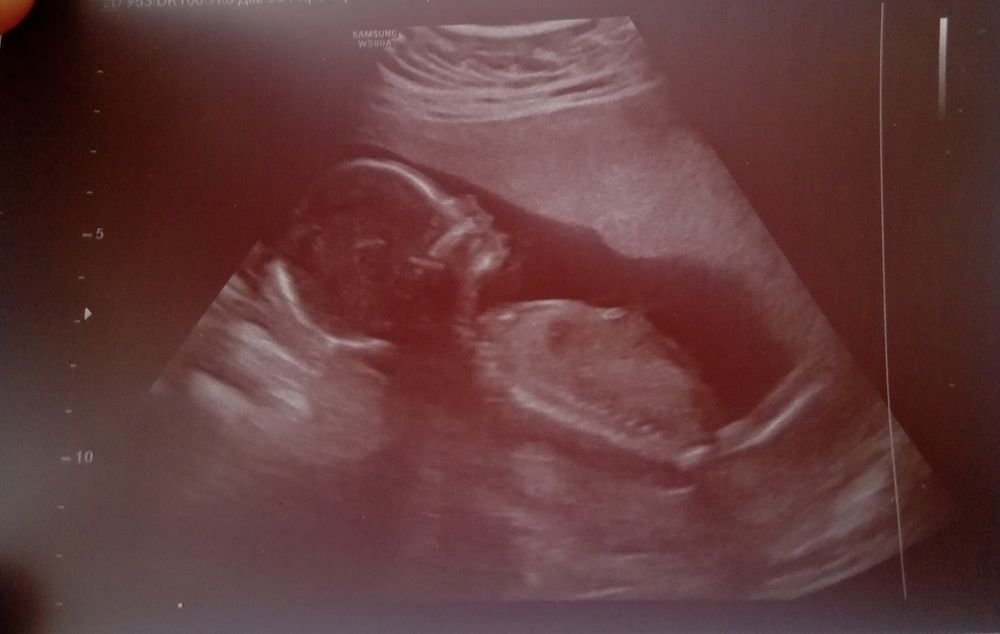

Прибавка веса +3,1 от добеременного.Ну и покажу малышку от начала до 20-й недели)))))